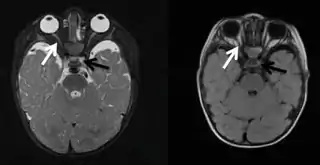

![]() Hipoplasia de nervio óptico señalada con una flecha blanca, la flecha negra señala aplasia chiasmal. | ||